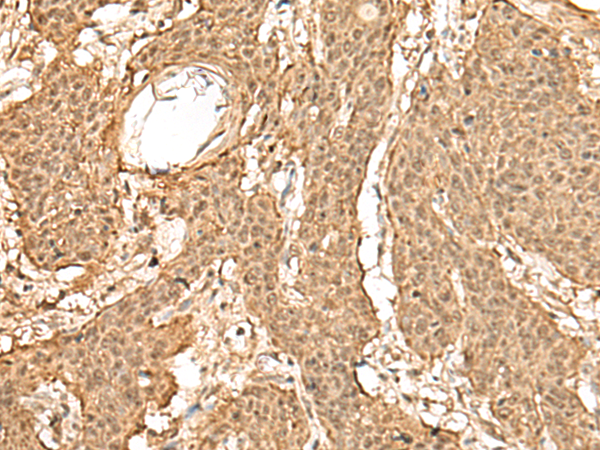

IHC positive control:

Human esophagus cancer and Human thyroid cancer

IHC Recommend dilution:

50-300